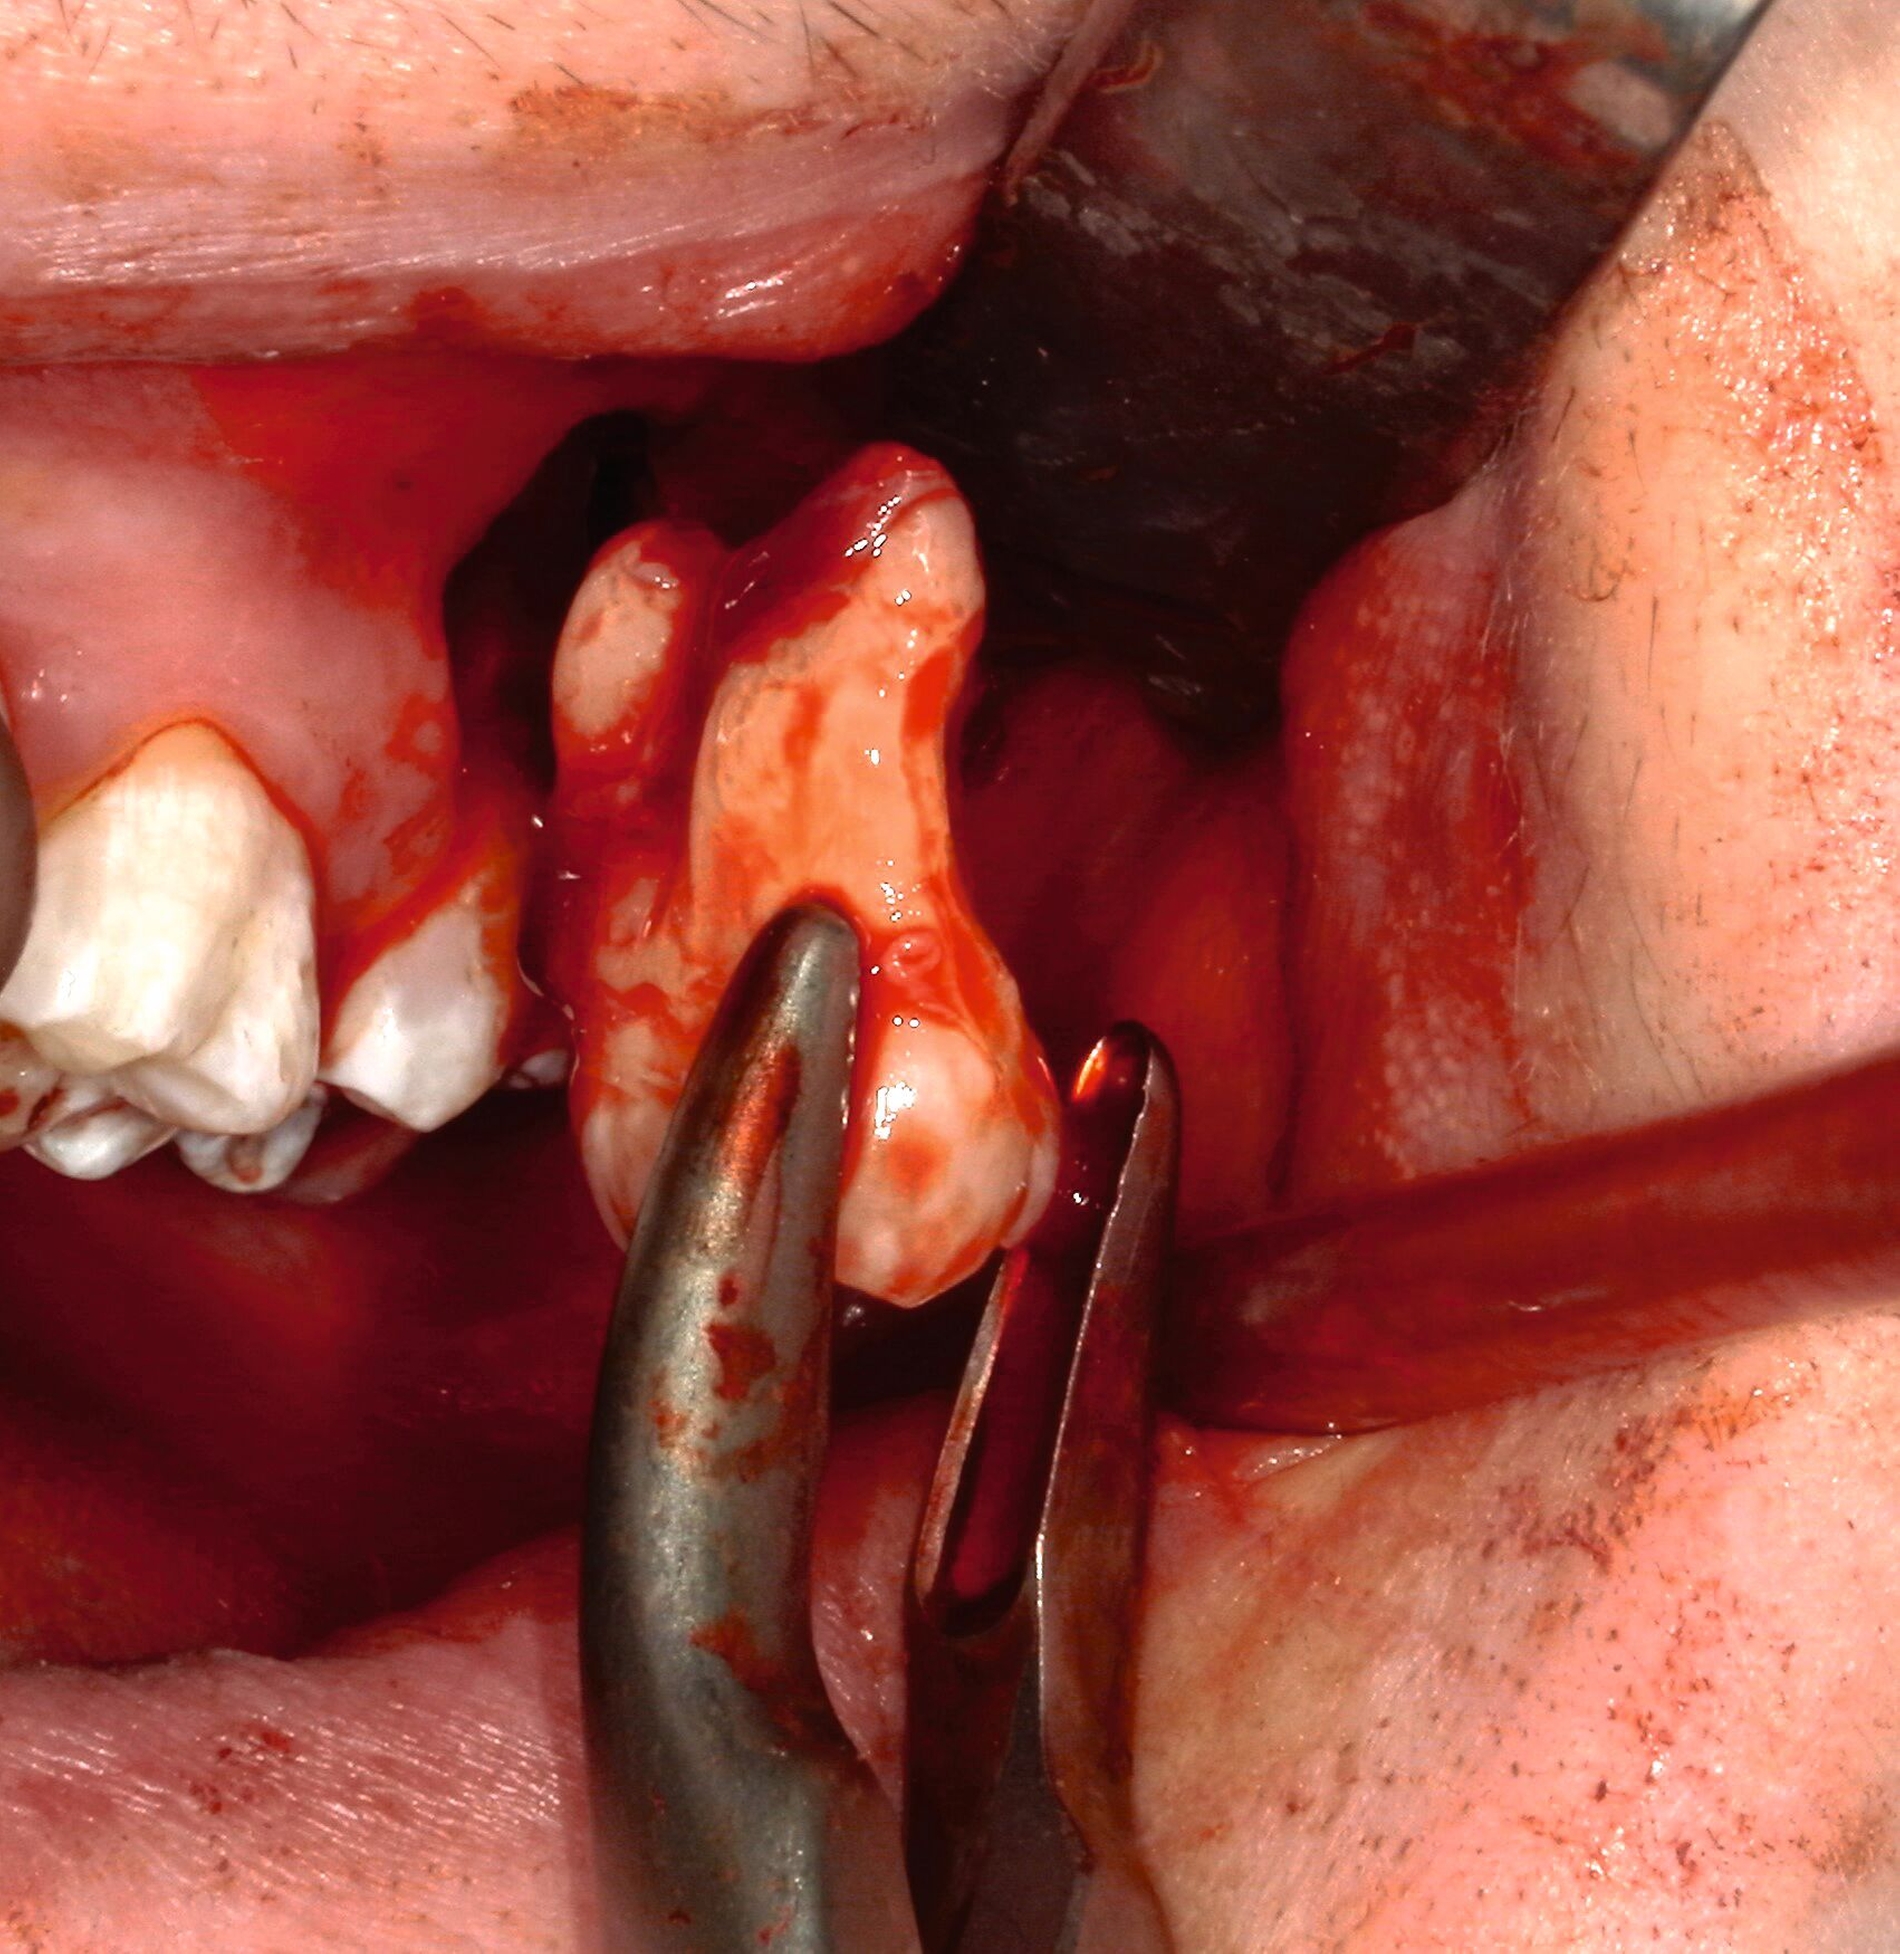

Nach Freilegung des Knochens kann ein Wundhaken nach Langenbeck eingesetzt werden sowie ein Bohr-Raspatorium zum Schutz des N. lingualis subperiostal lingual [Gutwald et al., 2019]. Unter Verwendung eines rotierenden Instruments (Kugel- und Lindemann-Fräse) oder Piezochirurgie wird der Knochen im Bereich der Zahnkrone abgetragen und diese freigelegt (Abbildung 8). Danach kann der Weisheitszahn vorsichtig mithilfe eines Bein‘schen Hebels anluxiert oder, falls dies noch nicht gelingt, mittels einer Lindemann-Fräse geteilt werden. Dabei wird am größten Kronendurchmesser die Krone mit der Fräse abgetrennt und die Wurzel anschließend separat entfernt (Abbildungen 9 und 10) [Gutwald et al., 2019; Schwenzer, 2019].